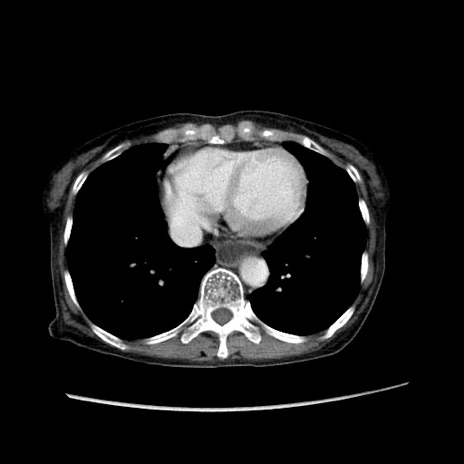

冠状断像